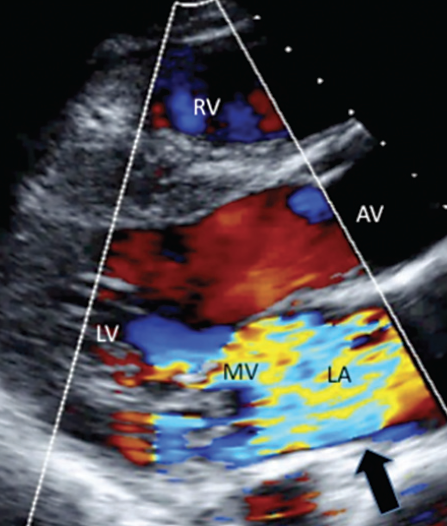

Alex Ianonne, DO; William Hicks, MD; Christopher Swift, DO; Christopher Malozzi, DO; Gregory W. Rutecki, MD

<p>For 5 days, a 30-year-old man has had fever, rigors, and diaphoresis. He admits to intravenous (IV) cocaine use.  His temperature is 38.6°C (101.4°F); pulse, 108 beats per minute...